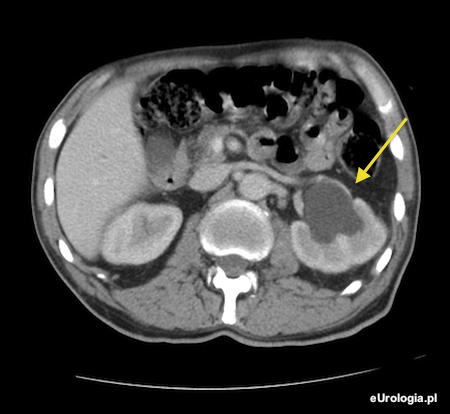

Wodonercze lewostronne